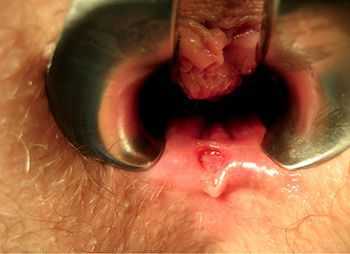

Как выглядит рак прямой кишки - фото

На фото рака прямой кишки можно заметить, что он значительно сужает просвет кишечника. Это является причиной запоров, переполненного живота, метеоризма.

На этом фото карцинома растет инфильтративно, охватывая стенку.